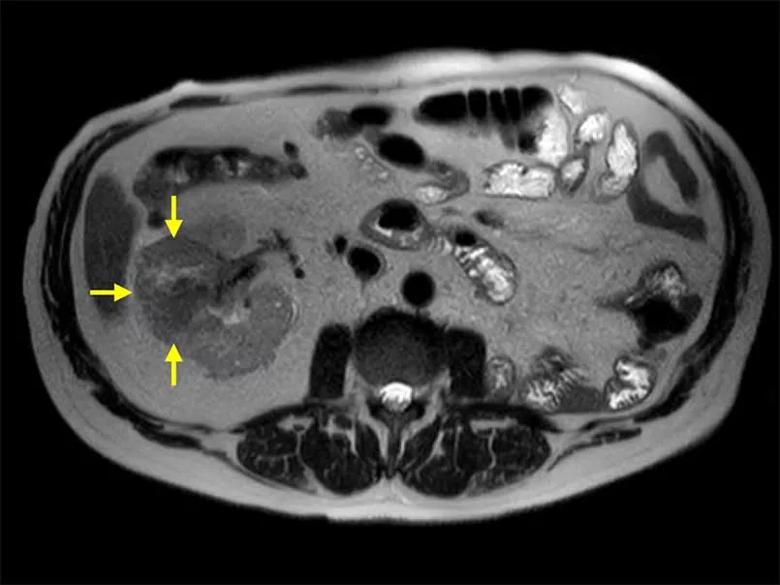

Figure 2. MRI of the abdomen (axial) showing a 6.6 cm right renal mass on a solitary kidney. R.E.N.A.L. score 10a